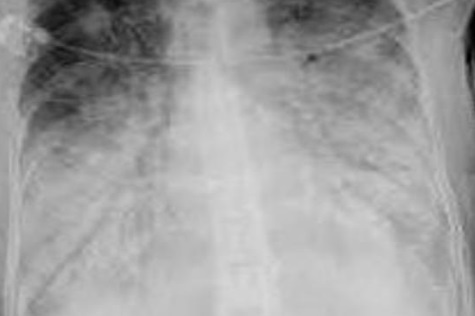

11

Q

¿Cuál es el diagnóstico?

A

Bronquiectasias